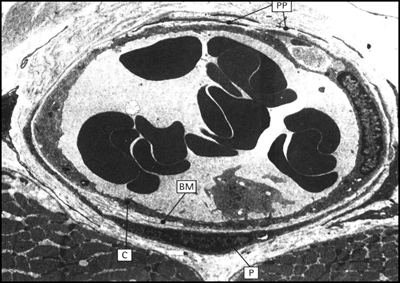

Διατομή φλεβιδίου σε ηλεκτρονικό μικροσκόπιο (εικόνα 2). Διακρίνονται η βασική

μεμβράνη, το κυτταρόπλασμα των ενδοθηλιακών κυττάρων και τα περικύτταρα.